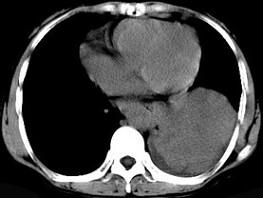

问题 女,55岁,胸痛伴咯血丝痰一周,胸部CT如图,最可能的诊断为 ( )

选项 A、多发性肺脓肿 B、结节病 C、左侧周围型肺癌并肺内转移 D、左侧中央型肺癌并肺内转移 E、转移性肺癌

答案 C